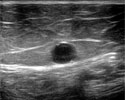

Все этапы лечения производятся под непрерывным ультразвуковым контролем.

"До" и "после" лечения.